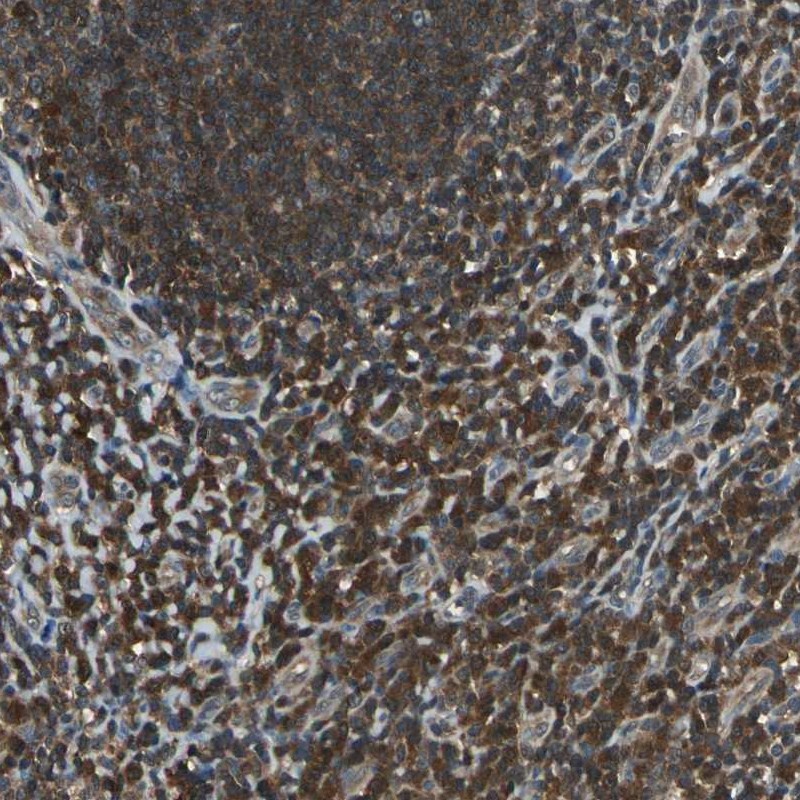

Immunohistochemical staining of human tonsil shows strong cytoplasmic positivity in germinal and non-germinal center cells.